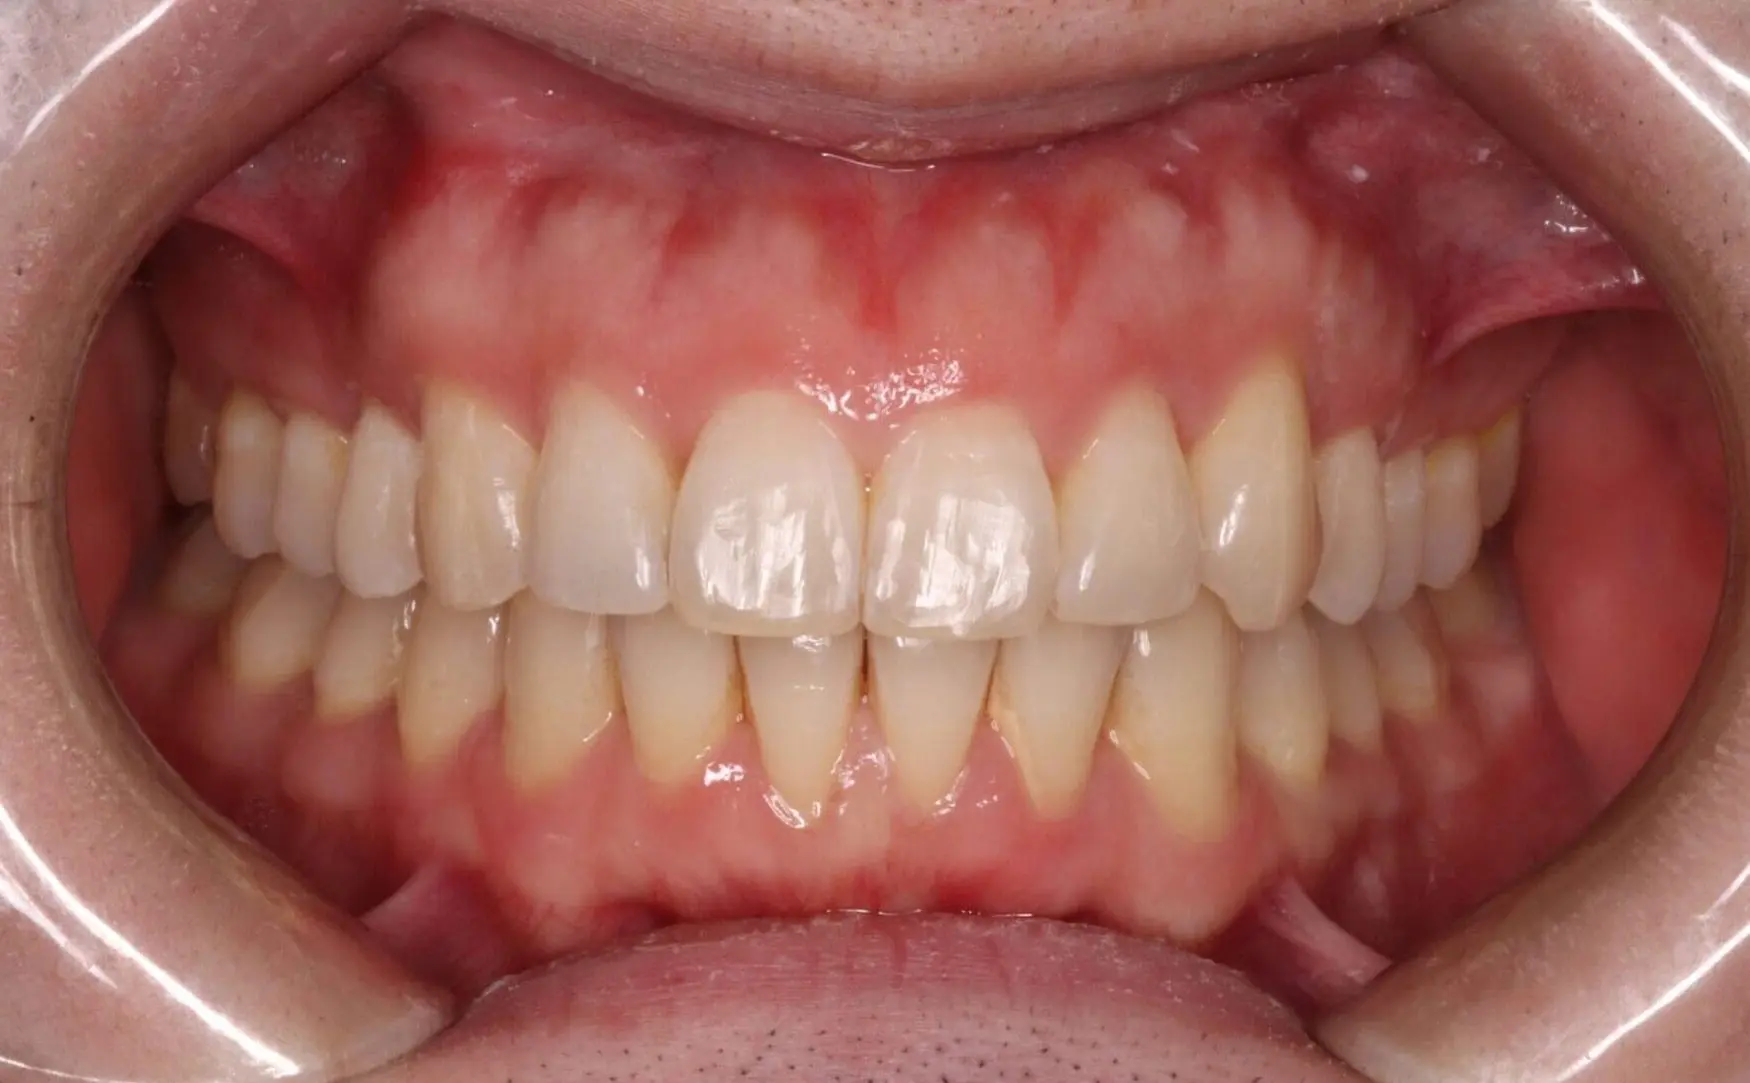

After

Before

Deep Bite